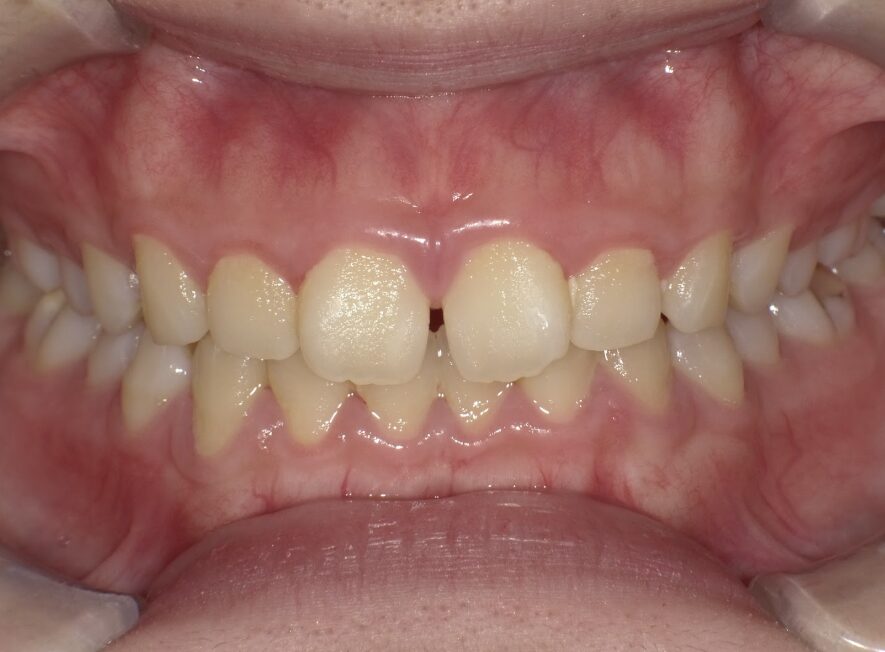

前歯のすき間が気になるを主訴に当院を受診され、前歯部空隙歯列(歯と歯の間に隙間が空いている状態)・過蓋咬合(上の歯が下の歯を深く覆いかぶさっている状態)・下顎前歯叢生(ガタガタ)を認めました。

IPRを使用してマウスピース型矯正装置(インビザライン)を使用し過蓋咬合及び叢生の改善を行いました。

年齢/性別10代女性

抜歯部位非抜歯

治療期間8ヶ月